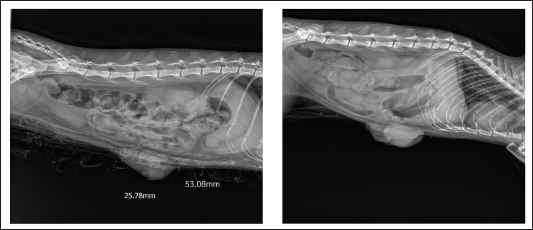

Radiography

On radiography images, the mammary gland tissue shows enlargement of the mammary glands with intact body wall (Fig. 3).

Fig. 3. Radiography images of mammary gland tissue showing enlargement of the mammary glands with intact body wall in different affected female cats.

Radiology was of little interest in cases of FMH, as lateral abdominal surveys only reveal the enlargement of the mammary glands with an intact body wall (Burstyn, 2010). In comparison, ultrasonography provides more valuable information about the assessment of lesion pattern and echogenicity. Similar findings have been reported (Payan, 2013). In the present study, medical treatment was administered to 25 cats using cabergoline drug administration (5 µg/kg once daily PO), which proved effective in the majority of treated cats, leading to substantial regression of mammary size within three to 6 weeks, as previously reported (Giménez et al., 2010; Akkuş and Yaprakcı, 2024).